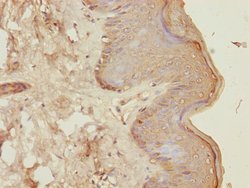

CENPK Polyclonal Antibody for Western Blot, IHC (P), ELISA

| ELISA, Immunohistochemistry (Paraffin), Western Blot | |